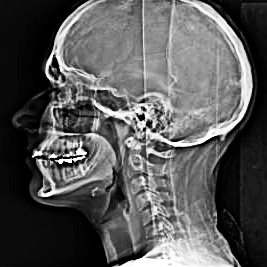

Vocal tract includes the areas from the glottis to the lips (see diagram). “In singing, the sound is generated by the vocal folds and resonated in the chamber of air defined by the vocal tract”2 .

Throughout our lives we use unconsciously these mechanisms to talk, sing, imitate sounds or nuances and express in different ways. Voice is an instrument we cannot completely see or feel, but the improvement of technology with the examples of Χ-ray, MRI and Laryngoscopy, bring scientific conclusions that help the imagination of vocalists regarding awareness, kinaesthesia and understanding of the vocal mechanism.